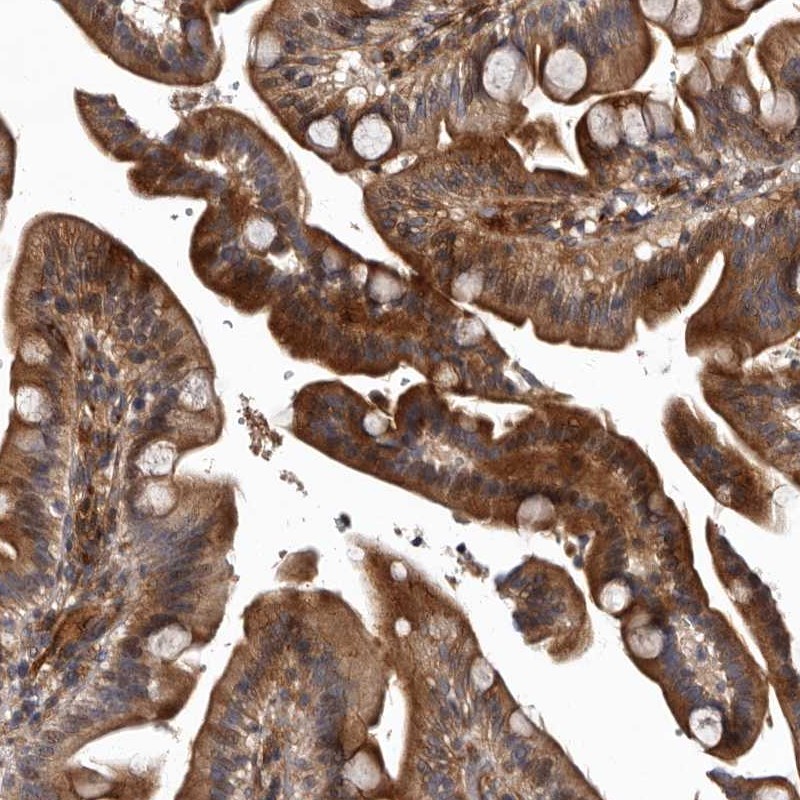

Immunohistochemical staining of human duodenum shows distinct cytoplasmic positivity in glandular cells.